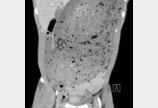

“위장 터질 뻔” 3kg 햄버거 30분 만에 먹은 男…CT 찍어 보니음식 빨리먹기에 도전한 싱가포르 남성이 위가 과도하게 팽창해 터질 뻔한 사례가 최근 국제 의료 학술지에 보고됐다.영국 데일리메일은 11일 소화기병학(Gastroenterology) 저널을 잉용해 싱가포르의 30세 남성이 햄버거 빨리 먹기 대회에 참가했다가 겪은 일을 소개했다.이름이 공…2025-03-12 14:41:00